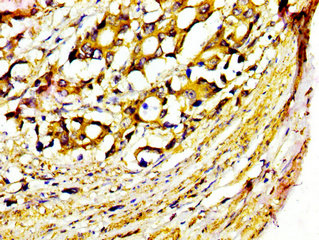

IHC image of CSB-PA015055LA01HU diluted at 1:400 and staining in paraffin-embedded human gastric cancer performed on a Leica BondTM system. After dewaxing and hydration, antigen retrieval was mediated by high pressure in a citrate buffer (pH 6.0). Section was blocked with 10% normal goat serum 30min at RT. Then primary antibody (1% BSA) was incubated at 4°C overnight. The primary is detected by a biotinylated secondary antibody and visualized using an HRP conjugated SP system.